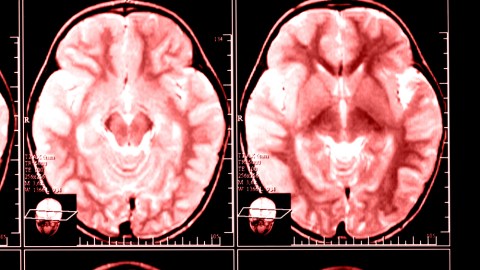

By analyzing activity in the brain’s visual cortex using fMRI scanners, researchers are able to know what an individual has been reading without any reference to the actual document itself. To do so, neuroscientists at a Dutch university taught a computer program how pixels from brain scans correspond to individual pixels in letters of the alphabet. While the study was limited to determining single letters seen by the experiment’s subjects, the results confirm that reconstructing brain images is an effective way to reconstruct what someone has seen.

The achievement improves on prior research which reconfigured the cerebral images of a person watching a video such that the rough outline and color of a shape, say of a tropical parrot, appeared on a computer screen. Researcher Marcel van Gerven, who led the Dutch experiment, said: “Our approach is similar to how we believe the brain itself combines prior knowledge with sensory information. For example, you can recognize the lines and curves in this article as letters only after you have learned to read. And this is exactly what we are looking for: models that show what is happening in the brain in a realistic fashion.”